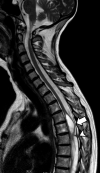

Adhesive arachnoiditis is a rare condition, often complicated by syringomyelia. This pathologic entity is usually associated with prior spinal surgery, spinal inflammation or infection, and hemorrhage. The usual symptoms of arachnoiditis are pain, paresthesia, and weakness of the low extremities due to the nerve entrapment. A few cases have had no obvious etiology. Previous studies have reported one family with multiple cases of adhesive arachnoiditis. We report a second family of Belgian origin with multiple cases of arachnoiditis and secondary syringomyelia in the affected individuals.